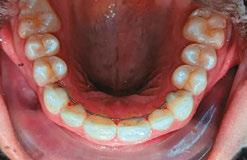

Patient J, a 39-year-old female, (Figures 1, 2, 3, 4, 5, 6) came to the office with concerns about difficulties chewing food and experiencing dry mouth upon waking up in the morning. Additionally, her partner was disturbed by her snoring. Upon examination, several issues came to light:

Figure 1: Swallowing with tongue trust

Figure 2: Anterior view before treatment

Figures 3 and 4: 3. Right side before treatment. 4. Left side before treatment

Figures 5 and 6: 5. Upper arch before treatment. 6. Lower arch before treatment